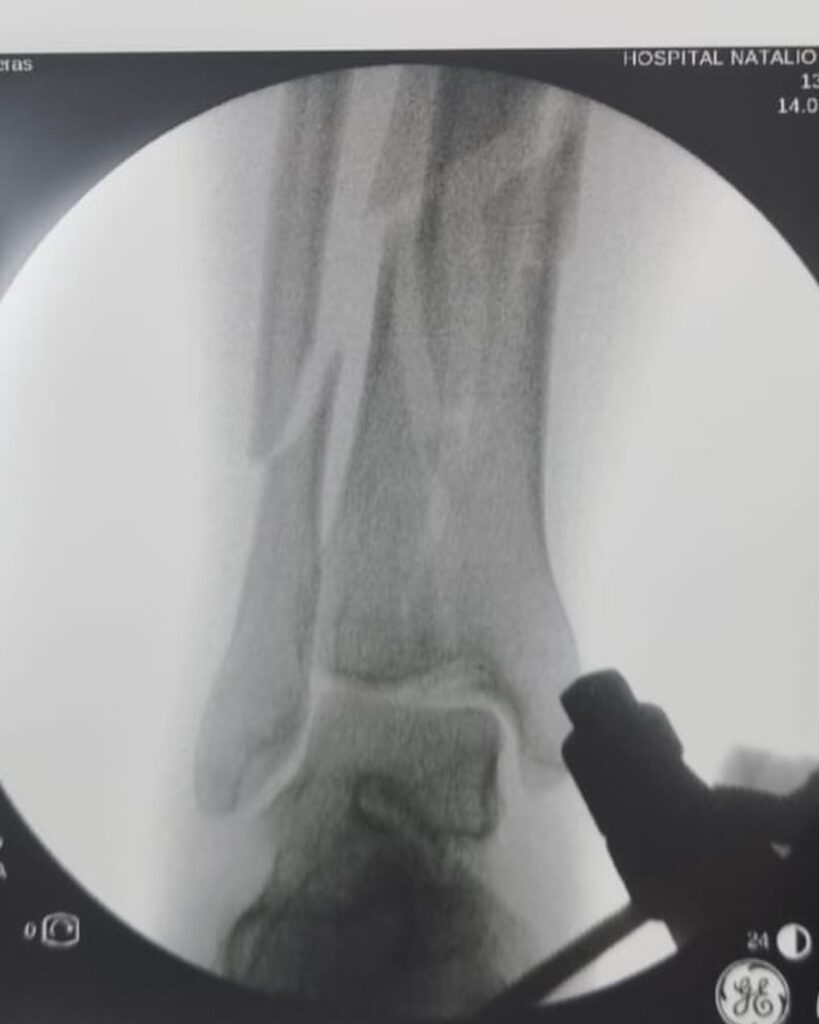

El manejo inicial de una fractura compleja de tibia representa un punto de inflexión en el proceso de recuperación del paciente. Tal como lo destacó el Dr. Escobar, la fijación externa emerge como una herramienta invaluable en esta etapa crítica.

- Estabilización inmediata: Al unir los fragmentos óseos de manera externa, se proporciona una estabilidad que reduce el dolor, disminuye el riesgo de complicaciones vasculares y nerviosas, y mejora el pronóstico de las partes blandas.

- Facilita la cirugía definitiva: La fijación externa permite abordar la fractura de manera más controlada y precisa en una segunda intervención. Al reducir el edema y la inflamación, se facilita la exposición quirúrgica y se minimizan las complicaciones intraoperatorias.

La elección del tipo de fijador externo y el protocolo de tratamiento dependerán de diversos factores, como la localización y gravedad de la fractura, el estado de las partes blandas y las condiciones generales del paciente. Es fundamental que la decisión sea tomada de manera multidisciplinaria, involucrando al traumatólogo, el cirujano ortopédico y otros especialistas según sea necesario.